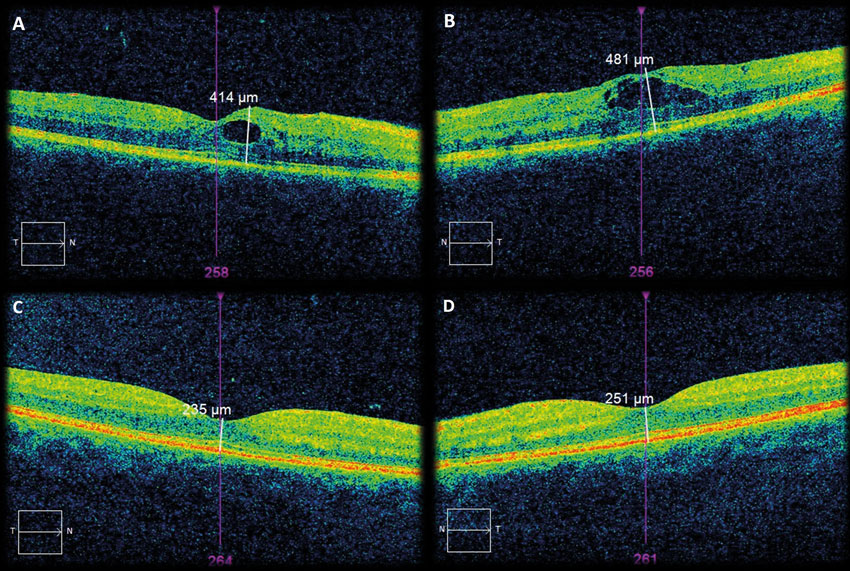

Figure 1: OCT images of right eye (A) and left eye (B) taken at 31 weeks gestation,

and repeat OCT images of right eye (C) and left eye (D) taken at six weeks postpartum.

Her corrected visual acuity was 6/18 in the right eye (RE), 6/24 in the left eye (LE), with improvement to 6/12 with pinhole for both eyes (BE). BE demonstrated clinically significant macular oedema, confirmed on optical coherence tomography (OCT) which showed centre involving diabetic macular oedema with retinal thickening of 414μm (RE) and 481μm (LE) (Figure 1 A&B). In addition, her RE showed signs of early / non-high-risk proliferative diabetic retinopathy (PDR), with new vessels on the right optic disc measuring less than 1/3 disc diameter. Her LE showed signs of severe non-proliferative diabetic retinopathy (NPDR). Unfortunately additional fundus photographs from that consultation are not available.

Her visual symptom self-resolved two days after delivery of the baby. Repeat OCT at six weeks postpartum showed resolution of macular oedema in both eyes; 235μm (RE) and 251μm (LE) with improvement of visual acuity to 6/9 (BE) (Figure 1 C&D). Her diabetic retinopathy progressed and was treated with PRP carried out at four months postpartum but her resolved DMO remained stable with 6/9 BE.